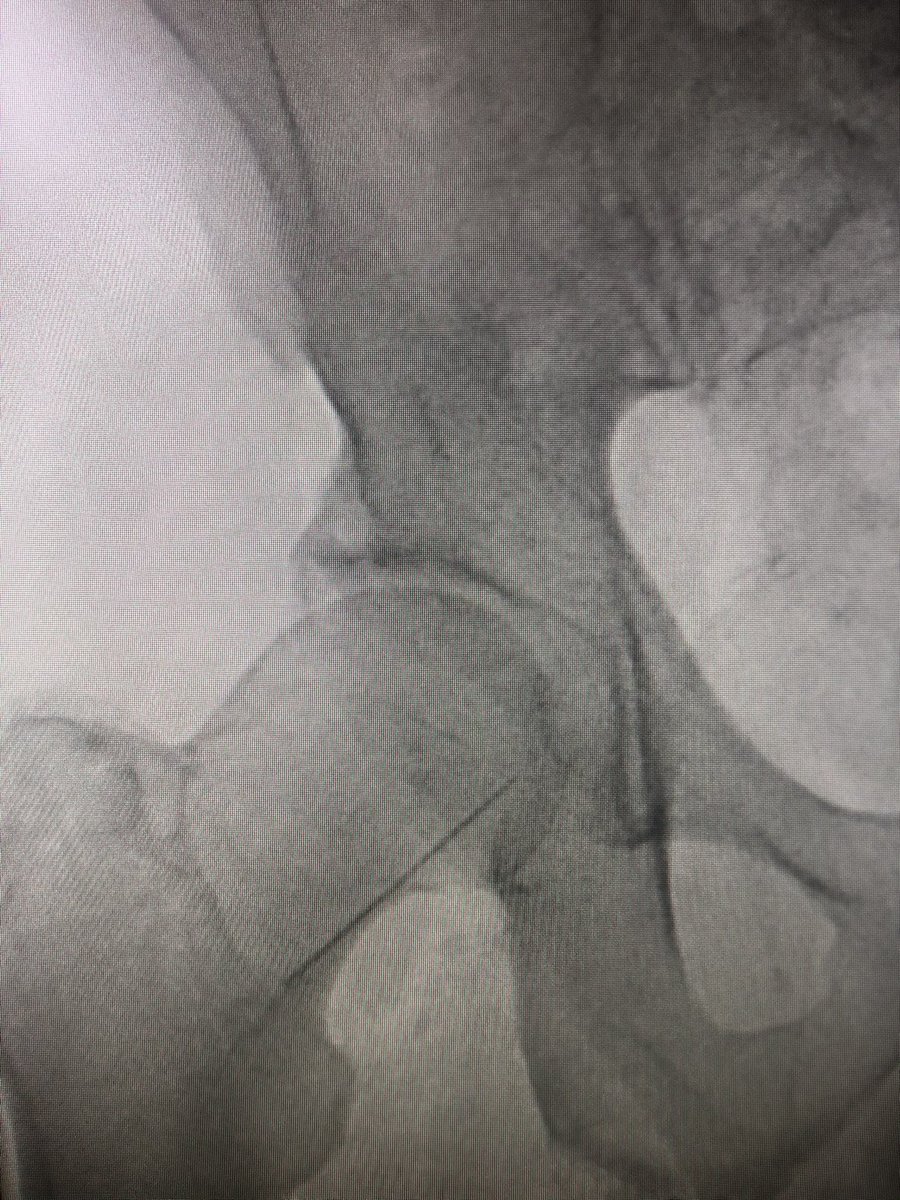

Step 3 - cautiously insert guidewire. #FluoroTheWire as it courses the artery. Observe its behavior and incorporate this into what sheath you should use for the procedure you need. I have started taking a quick #FluoroStore to show angle of needle and wire. #JointCathConference

Step 4 - #AccessAngio through micro access. tip - keep guidewire in and attach #CoPilot and inject. Protects by injecting into vessel and not the wall! #PreventDissection Remember to angle to show SFA and profunda. #JointCathConference